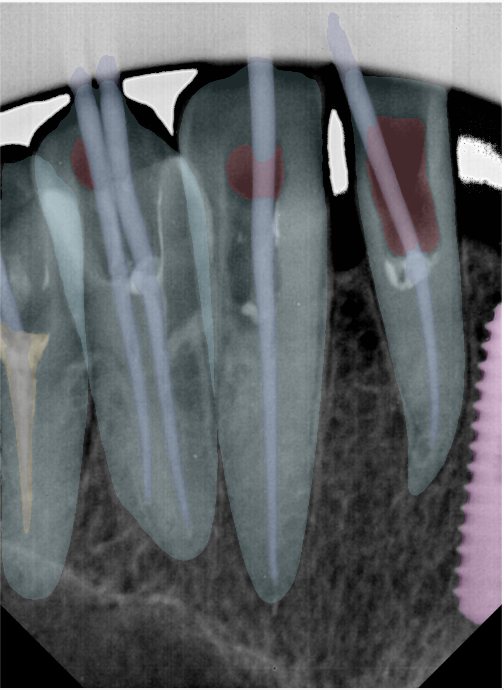

CR/DR 牙齿分割阶段记录

当前进展

- 完成了 CR/DR 牙齿相关分割训练

相关测试

遇到的问题

- 训练过程中出现过 mask 下移问题

- 部分结果会出现 box 填充异常

- mask 边缘仍然有比较明显的锯齿感